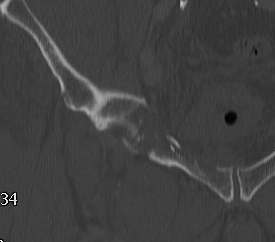

5. Transverse

- from greater sciatic notch to AIIS

- obturator foramen not fractured

High - above acetabulum

Low - through acetabulum

Complex / More than one primary fracture line

1. Posterior column & posterior wall

2. Transverse & posterior wall

3. T-shaped

- transverse through acetabulum

- inferior fracture line to obturator foramen

4. Anterior & posterior hemi-transverse

5. Both column

- Y Shaped transverse above acetabulum